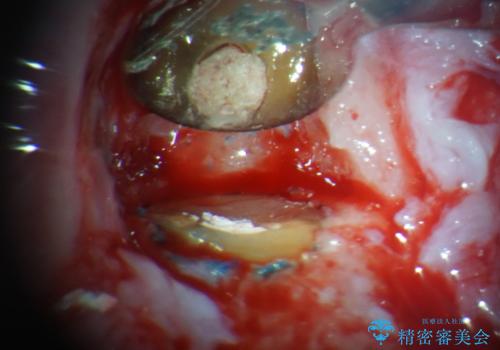

根管治療後に痛みは軽減しましたが、僅かな痛みが続くとのことで、レントゲン写真では病変は認められなかったものの、歯根端切除を行うこととしました。処置後は痛みは全くなくなり、安心して補綴治療を行うことができました。